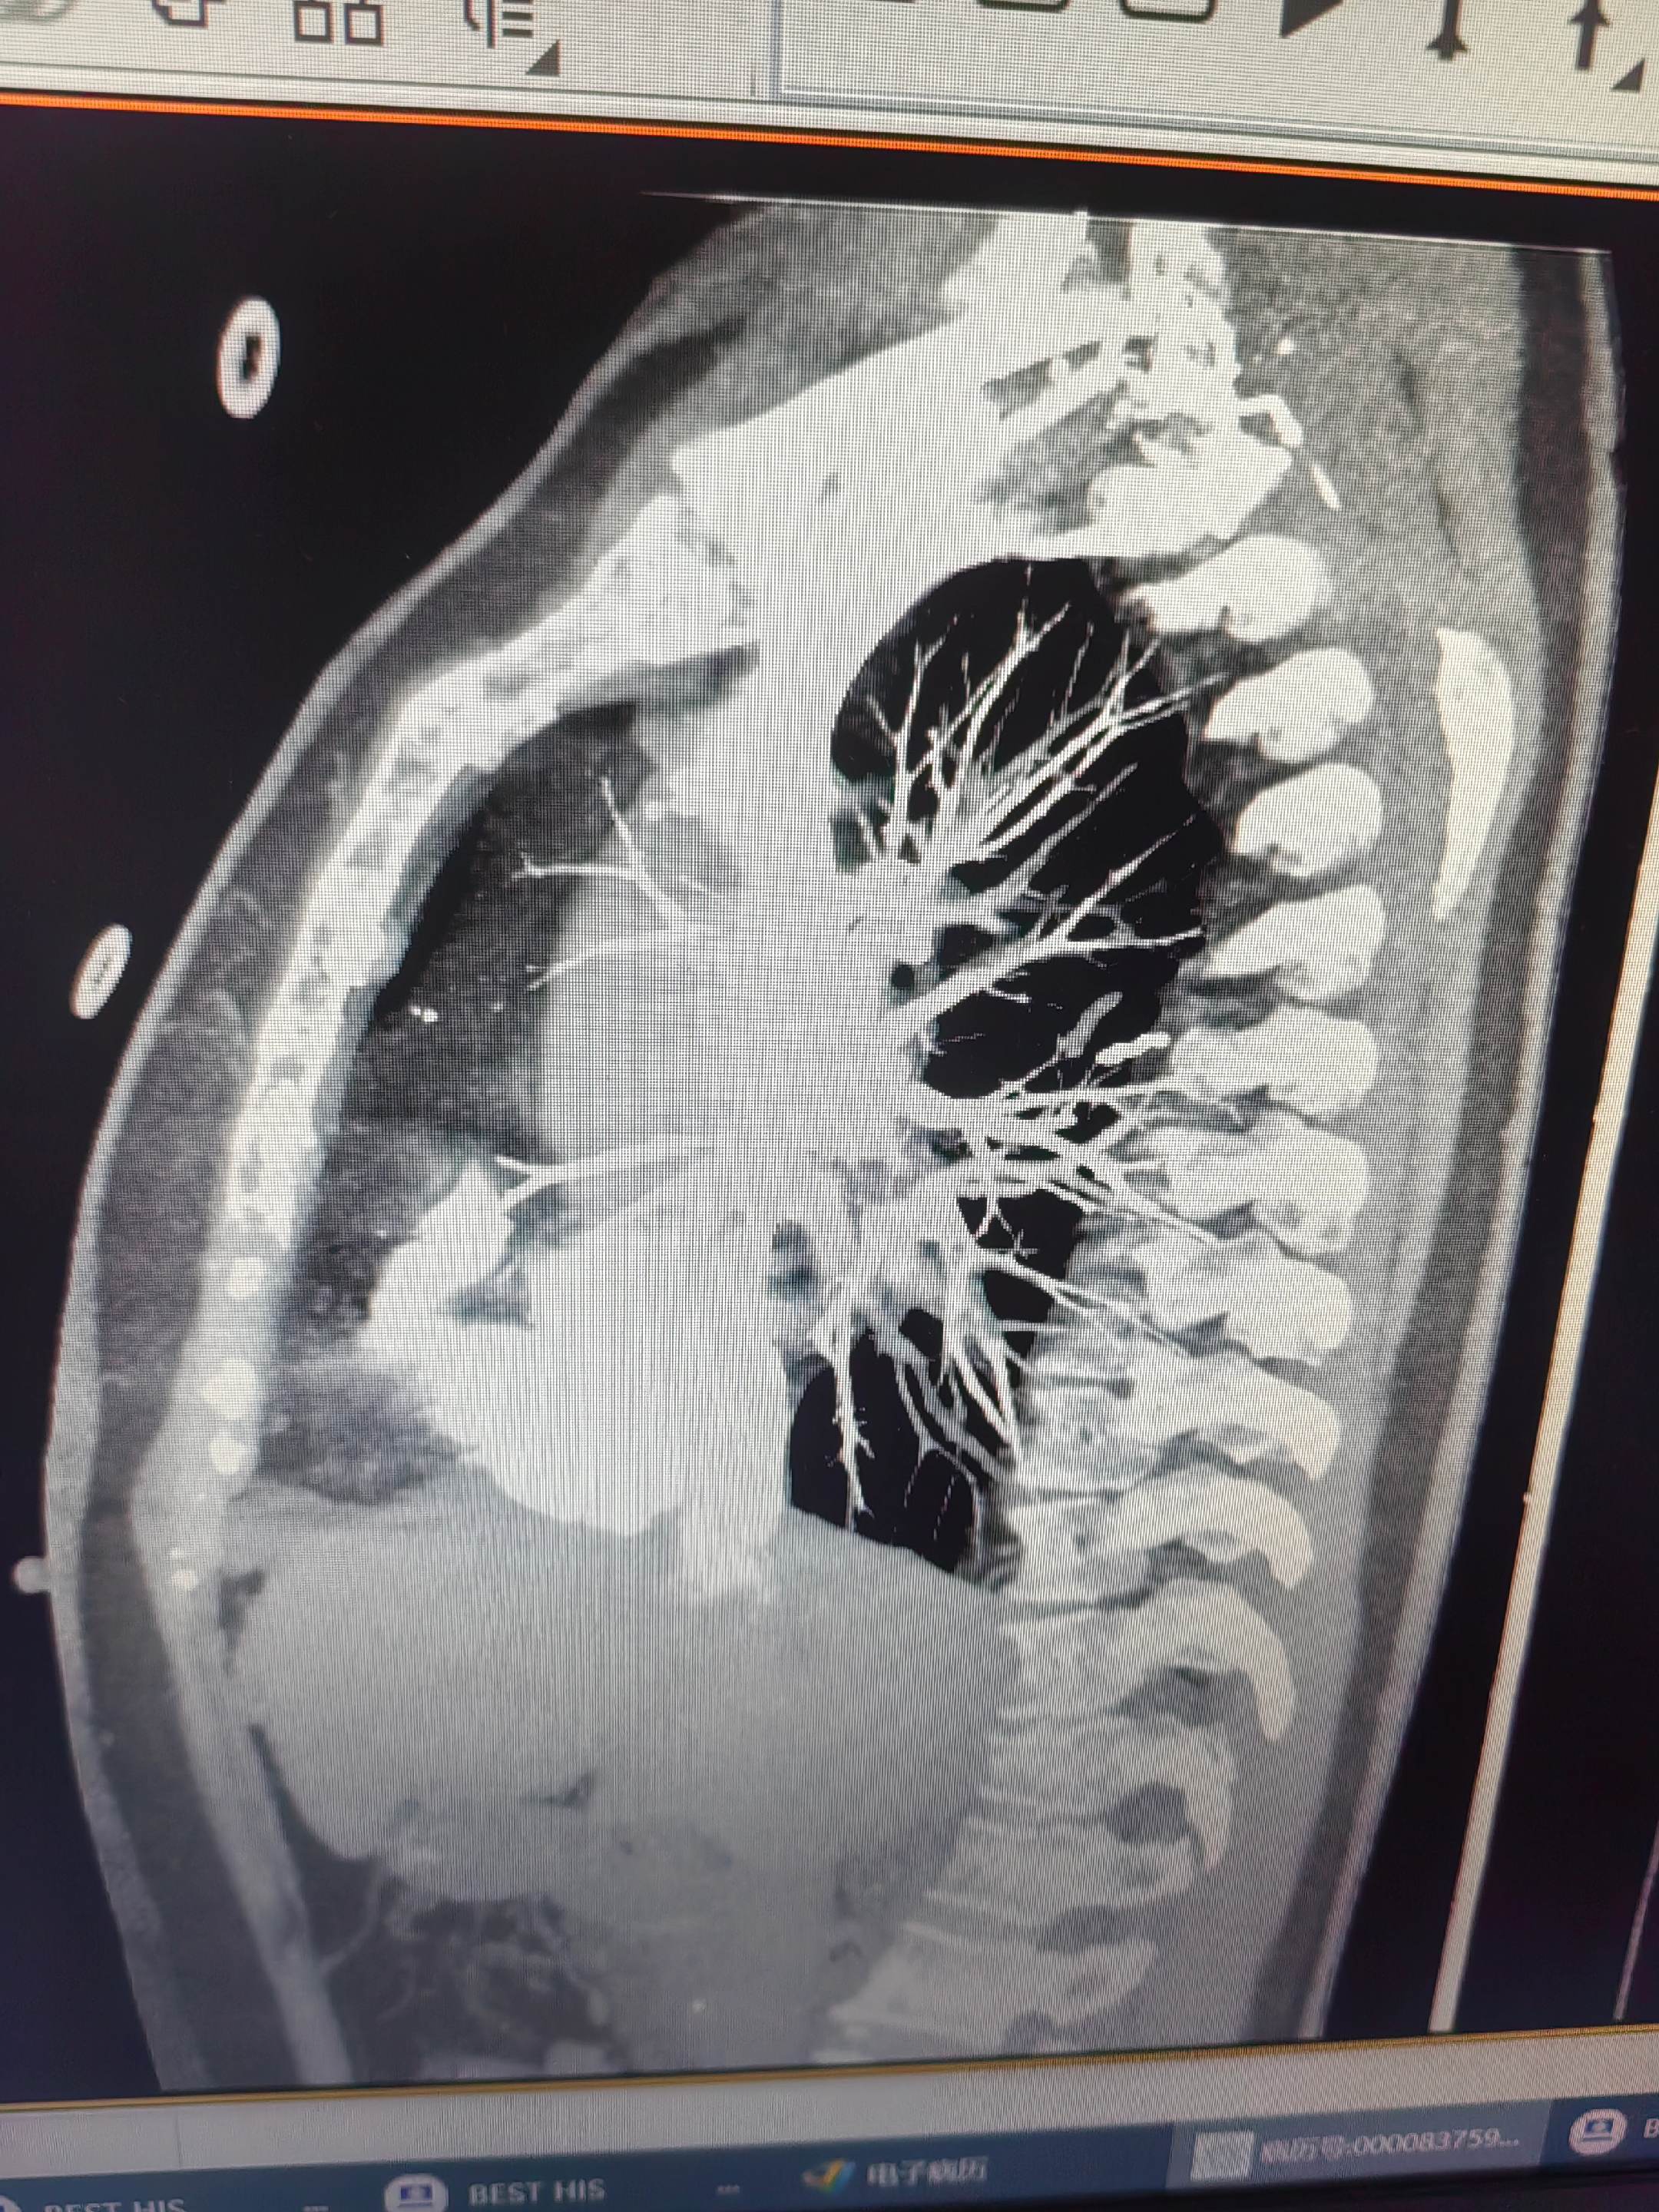

肺栓塞。